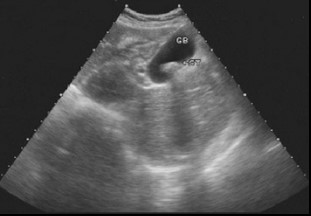

胆石症的典型表现:胆囊或胆管内形态稳定的强回声团,后方伴声影,强回声团随体位改变而移动。合并急性胆囊炎时胆囊可增大,慢性胆囊炎胆囊多缩小,胆囊壁增厚,边缘毛糖,回声增强。